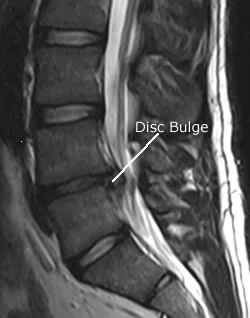

You can see a disc bulge of the low back on this MRI

In my clinic, there are certain orthopaedic tests that can be done, coupled with range of motion testing, deep tendon reflexes, muscle testing and sensation testing. That being said, the gold standard to determine if a disc issue is present is an MRI.